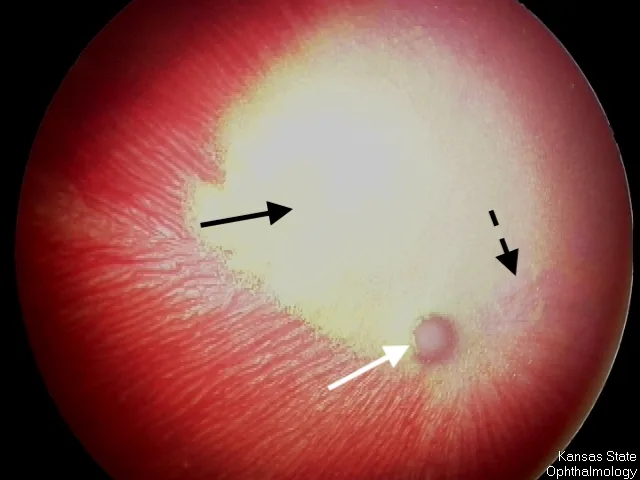

Mydriasis is typically the initial sign of retinal degeneration, but fundic signs can include tapetal hyperreflectivity, retinal vessel attenuation, increased tapetal reflectivity, and optic nerve atrophy (Figures 1 and 2). Although some affected cats regain vision, others are permanently blind.

Fundus of a 3-year-old spayed Siamese cat with advanced retinal degeneration following enrofloxacin administration. Marked vascular attenuation (dashed arrow), increased tapetal reflectivity (solid black arrow), and optic nerve atrophy (white arrow) can be seen. The fundus is subalbinotic, which allows visualization of the choroidal vessels in the nontapetal portion of the fundus. Subalbinism is a normal variation in cats with blue irises. Image courtesy of Kansas State University Ophthalmology